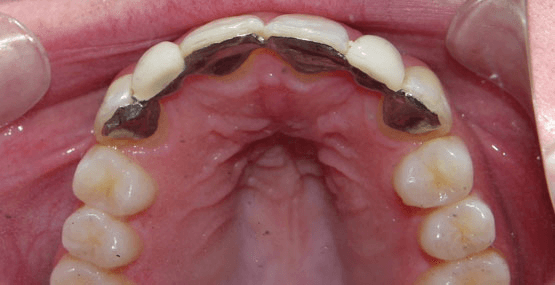

Ultimately, we chose to do two separate bridges out of an all-ceramic material, bonded only to the canines on each side. E.max lithium disilicate bridges from Ivoclar Vivadent 13-X and X-23, cemented by first air abrading the teeth, acid etching with Bisco’s Uni-etch 32% H3PO4 (aq) with BAC, and finally bonding in with Calibra Adhesive Resin cement as per recommended protocol. The results showcase a much more natural smile that’s both brighter and more resilient.